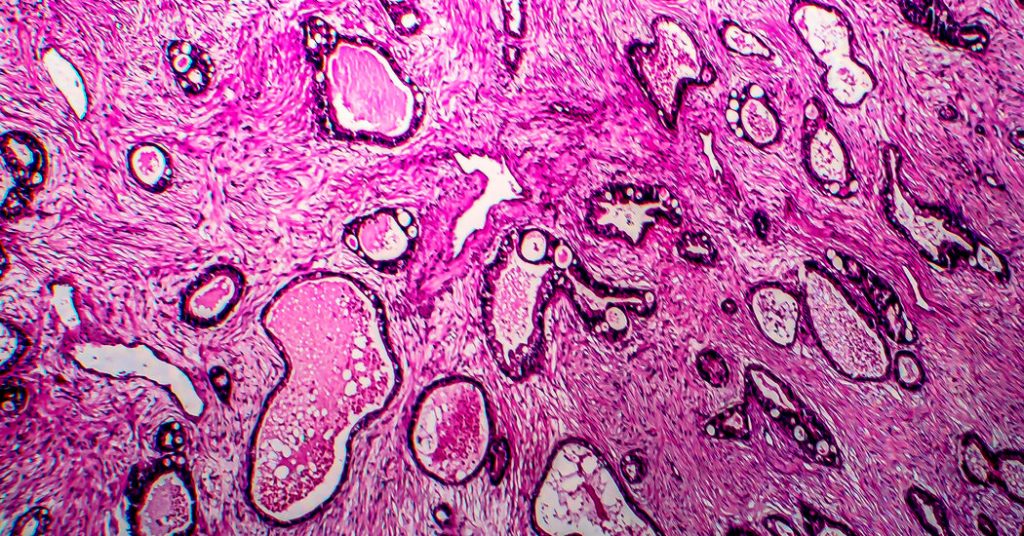

Tümör mikrobiyomu. İki yeni insan, kansern bakteri ve mantarlarla dolu olduğunu ortaya koydu. Bu sözde olay mikrobiyomu, onun kanser o kadar belirgin olduğunu kanıtlıyor ki, bilim adamları, bu mikropların kana dökülebilir mikrobiyal DNA’yı ölçerek gizli tümörlerin erken yaştaki bulmayı umuyor.

Rektum kanserleri. 18 rektum kanserlerinin aynı ilacı, dostarlimab’ı şaşırtıcı bir sonuç vermiş gibi görünüyor: Kanser, onun bir kullandığıda yokmuş gibi görünüyor. Uzmanlar, bu okuyucudan türetilen ilk inandığına inanılıyor.